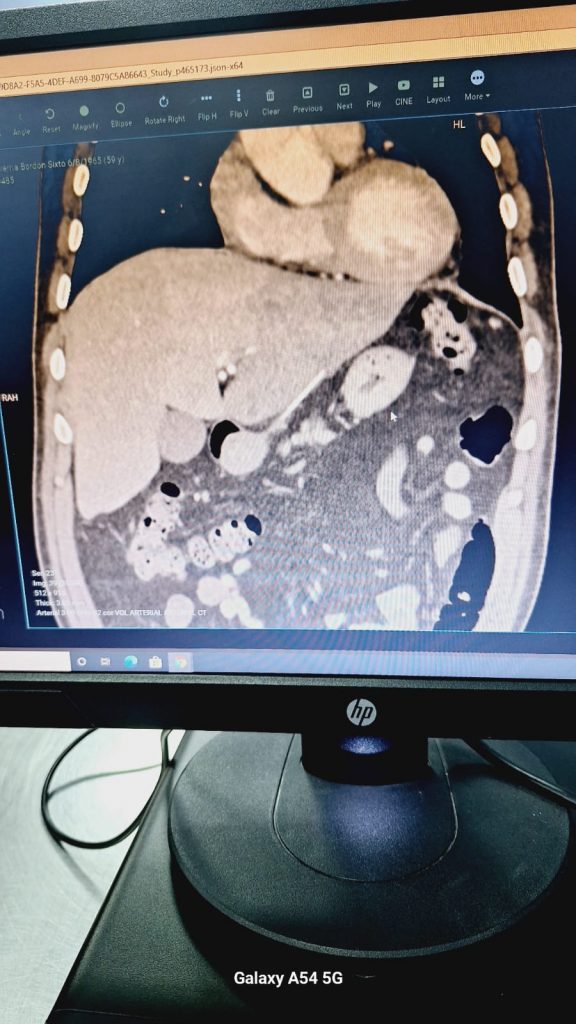

El paciente fue derivado al IPS Ingavi, donde se le realizó una tomografía contrastada del abdomen y los resultados revelaron la presencia de un cuerpo extraño entre el hígado y el estómago, lo que había causado un absceso en el hígado.

Fue evaluado por los especialistas de cirugía mínima invasiva; quienes se percataron que se encontraban con un objeto entre el hígado y el estómago ; profesionales solicitaron la reevaluación por cirugía general.